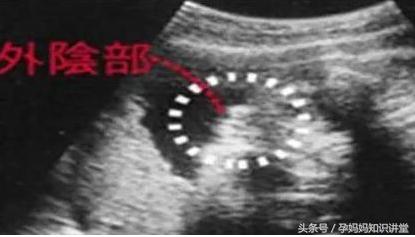

B超单看胎儿性器官

假如怀的是女孩,那麼可以看到三条线 。